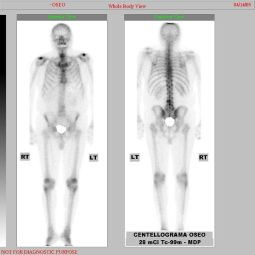

Metástasis óseas por cáncer de prostata

Envíado por Instituto Nacional de Cardiología y Cirugía Cardiovascular